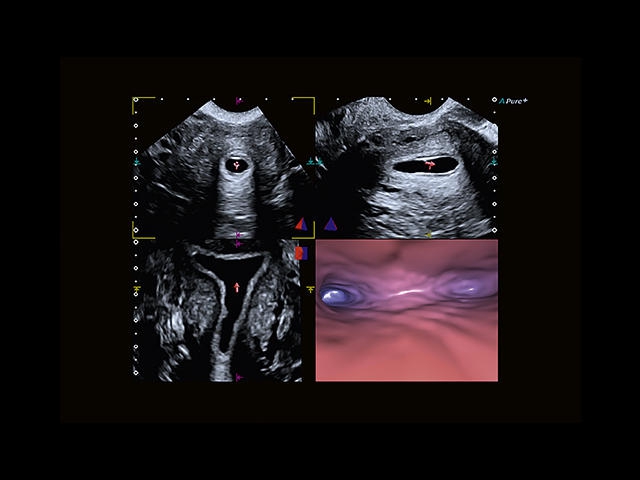

Обновленная версия легендарного УЗ-сканера. Стационарный аппарат экспертного класса Aplio 500 Toshiba NEW, визуализирует анатомические структуры в высоком разрешении. Модель позволяет выявить микрокальцификаты, новообразования, нарушения в работе сердца, сосудов и мышц. Присутствует функция виртуальной эндоскопии, 4D-сканирования, эластометрии тканей, УЗИ с контрастированием. За повышение качества изображения отвечают технологии ApliPure и Superb Microvascular Imaging. Первая задействует возможности пространственного и частотного кодирования, формирует цельный визуальный ряд с сохранением клинических маркеров. Вторая улучшает отображение микрососудистого русла, используя доплеровский эффект. Модель оснащена 21-дюймовым монитором, имеет 4 активных порта. Возможно подключение педиатрических, интраоперационных, лапароскопических и чреспищеводных датчиков.

• Fly Thru. Виртуальная эндосонография обеспечивает построение трехмерной модели полостей, протоков и сосудов в рельном времени, облегчает организацию инвазивных процедур и динамических исследований. Посредством Fly Thru можно установить шунты и стенты, проводить точные оперативные вмешательства.

• MicroPure. Высокотехнологичное решение в области выявления микрокальцификатов – маркеров новообразований злокачественного типа. Маркеры идентифицируются путем изучения затененных изображений целевого участка. Микрокальцификаты отображаются в виде белых пятен.

• SMI. Опция, упрощающая визуализацию микроциркуляторного русла. С ее помощью обследуются сосуды с низкой интенсивностью кровотока, изучаются наиболее тонкие структуры. SMI упрощает диагностику новообразований, минимизирует вероятность ошибки.